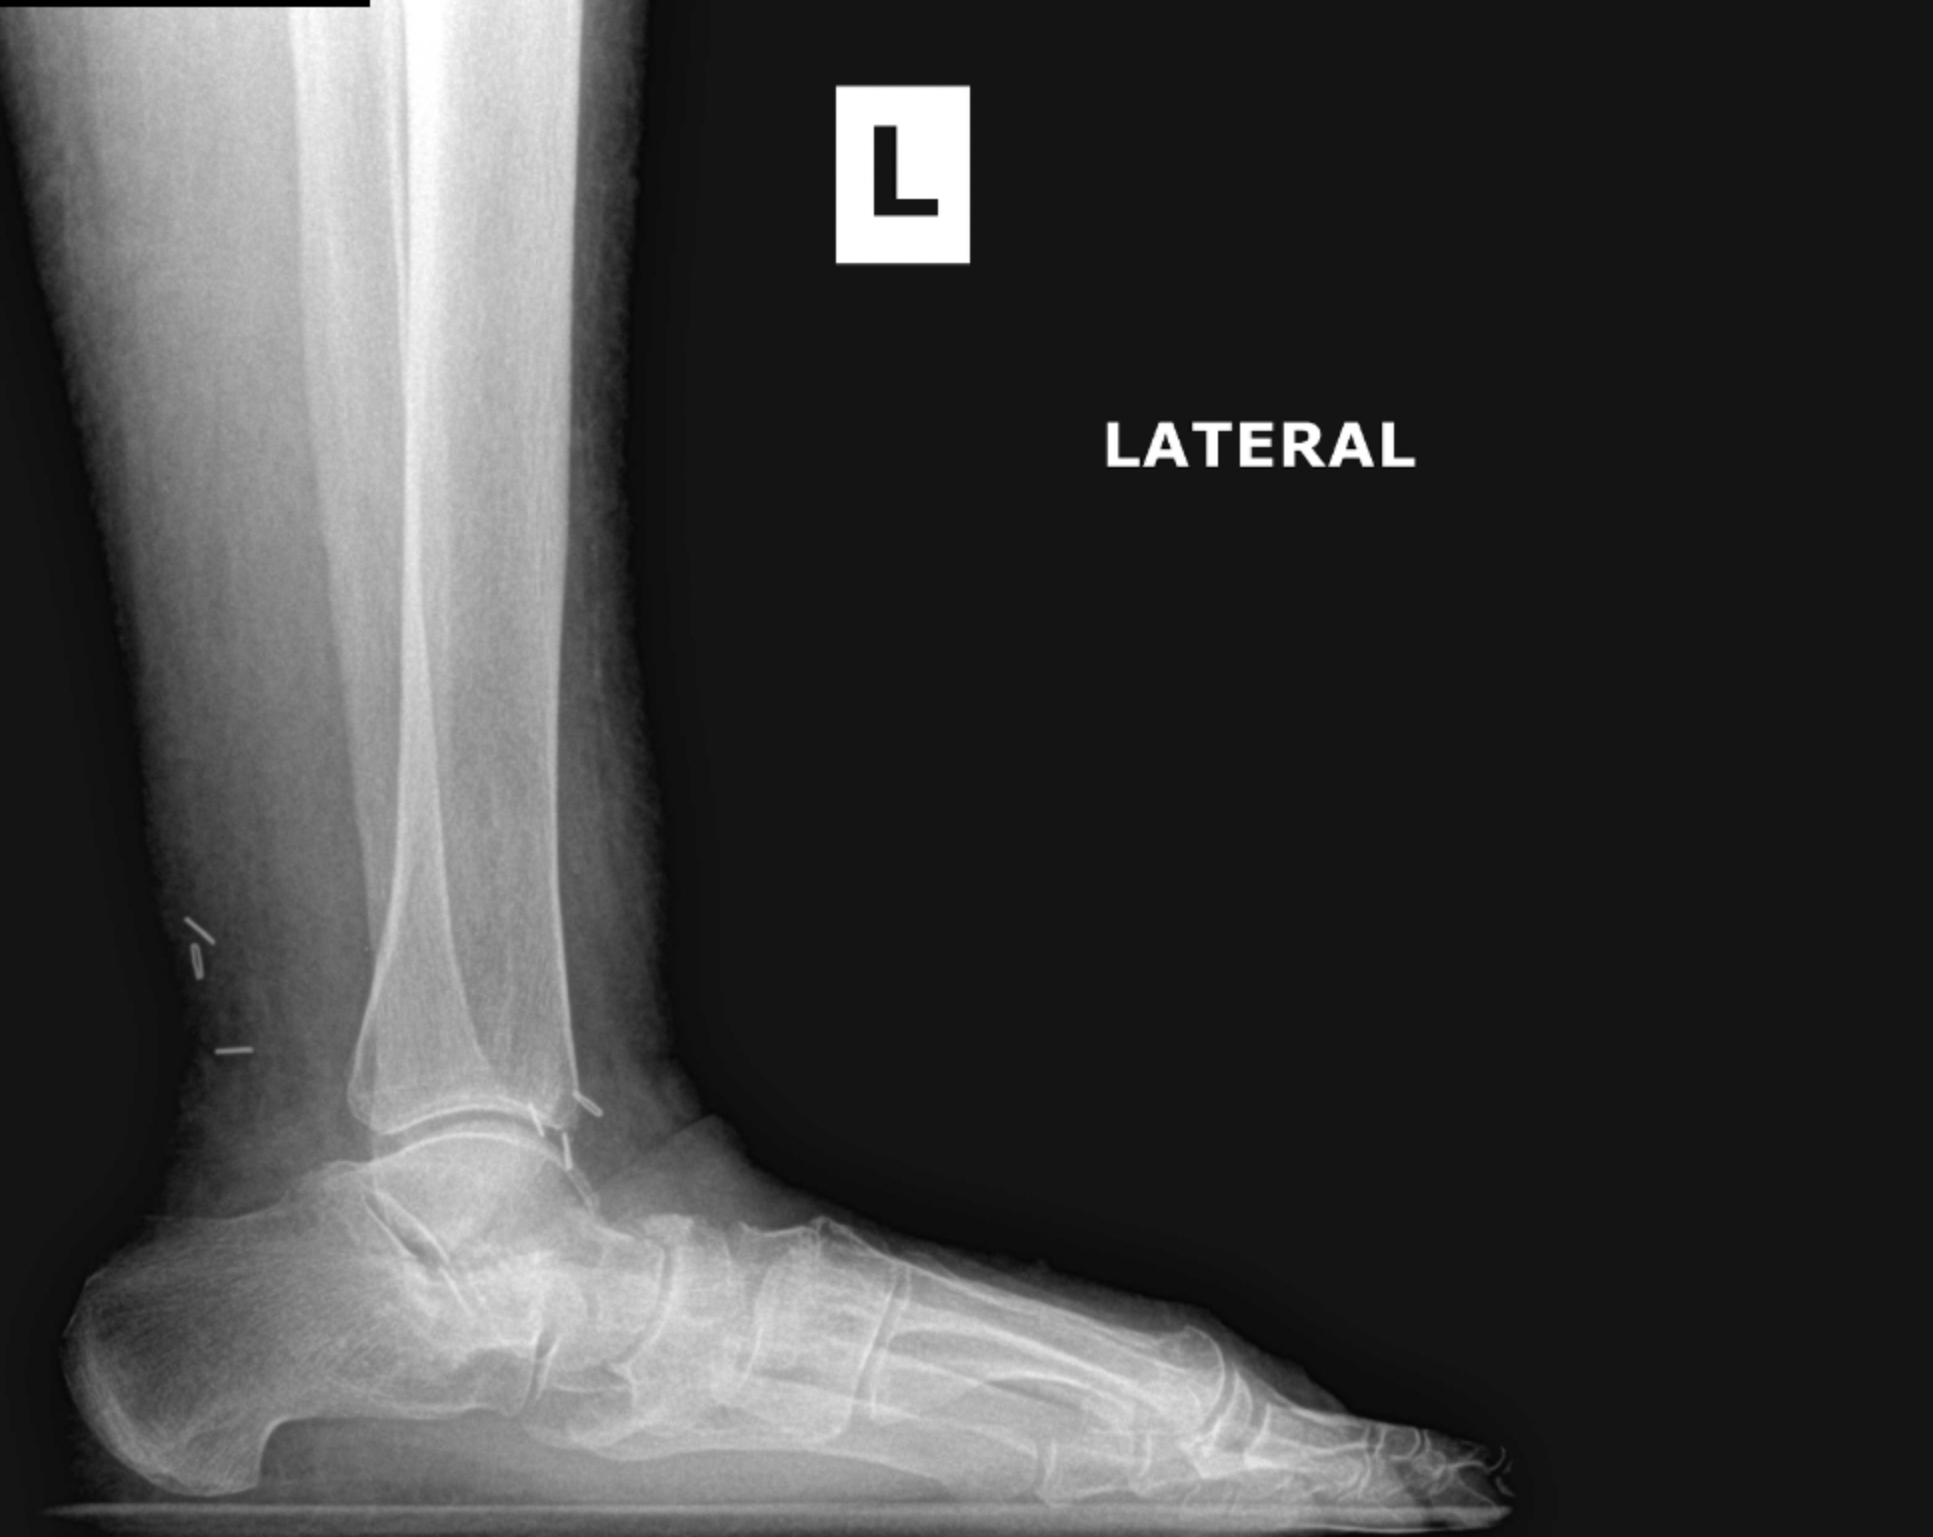

Arthritic flatfoot

Flatfoot deformity

Patient 1

Patient 2